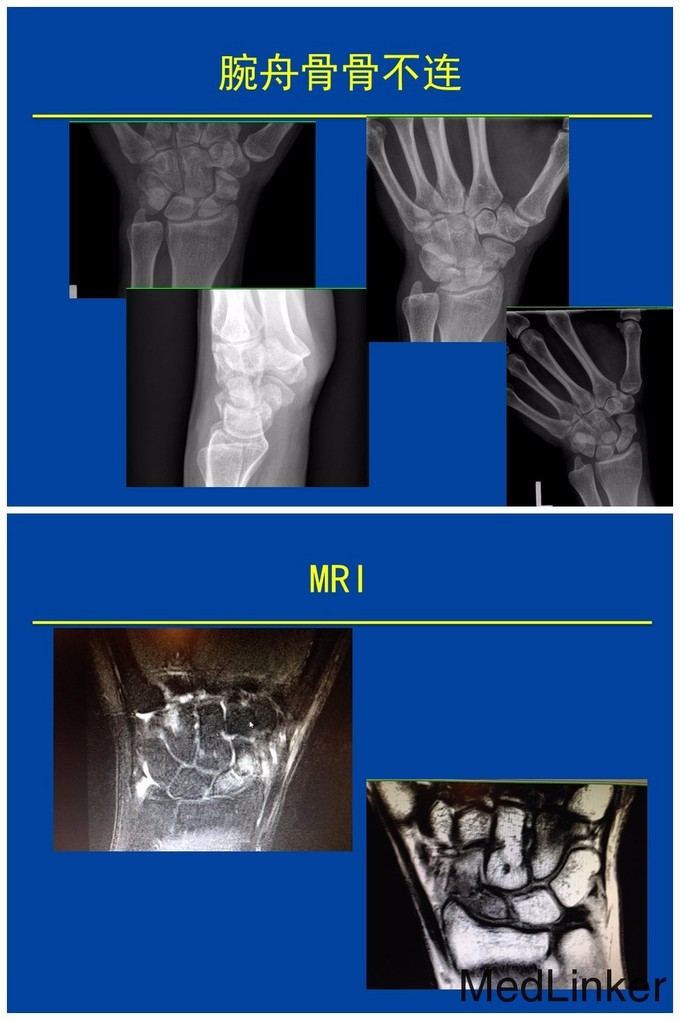

本篇学习目的是: 1 回顾腕舟骨骨折的基本诊断 2 探讨腕舟骨影像检查的几种方法 3 非手术与手术治疗的选择 4 腕舟骨骨不连的处理 Dawn M. LaPorte, MD Oorthopadic Surgery, Johns Hopkins 拉波特教授于麻省理工学院本科毕业后就读于约翰霍普金斯大学医学院。曾分别于翰霍普金斯大学医学院和柯蒂斯中心国家手与上肢外科完成住院医师培训。临床上致力于手和上肢外科。自2001年起已担任过8年的约翰霍普金斯大学住院医师培训项目负责人。现任约翰霍普金斯大学医学院骨外科教育副主席,美国手外科协会住院医师培训委员会主席(ASSH),骨科住院医师管理委员会和骨科科住院医师审查委员会委员。